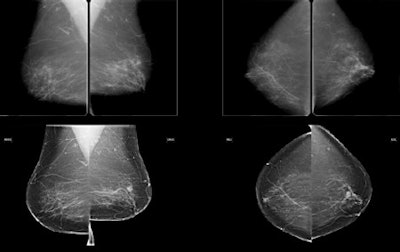

Subtle mass that was not recalled during screening, but detected on CAD. Top row: Exams that were not recalled during screening. Bottom row: Exams where lesion was detected in a later screening round. All images courtesy of Dr. Jaime Melendez.